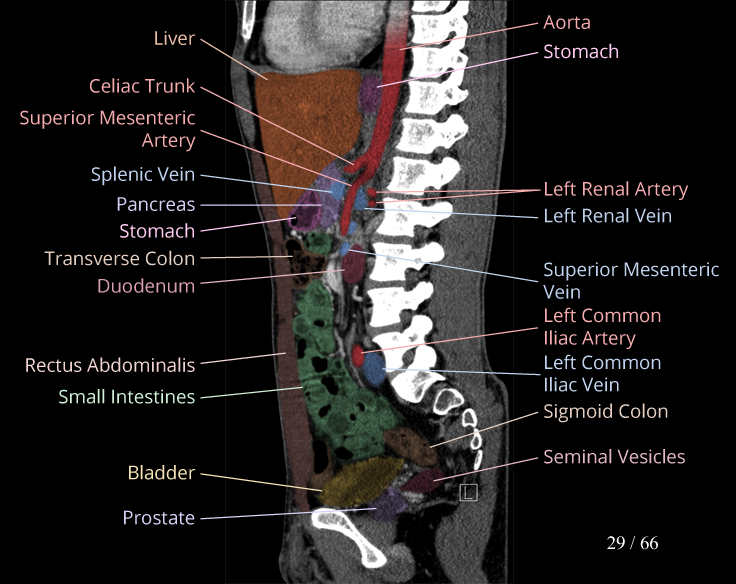

Body

Covers abdominal CT anatomy.